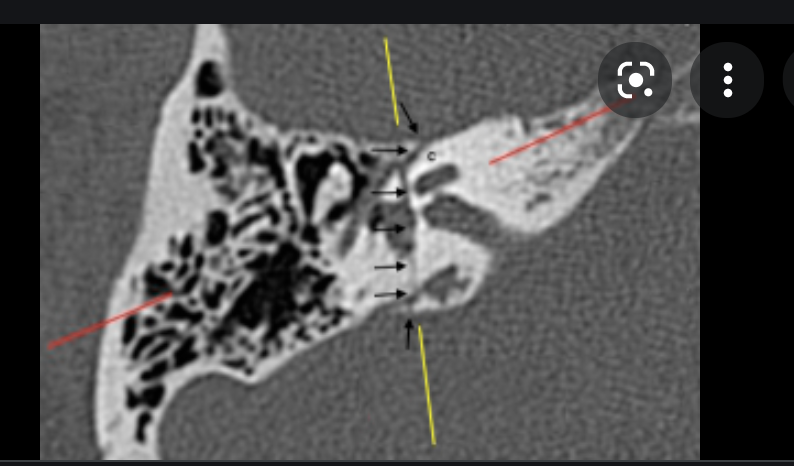

what are the 2 types of fractures of the temporal bone?

which is more common?

Typically involves?

Which one involves the ossicles?

Which one involves the TM?

which is more likely to cause facial paralysis?